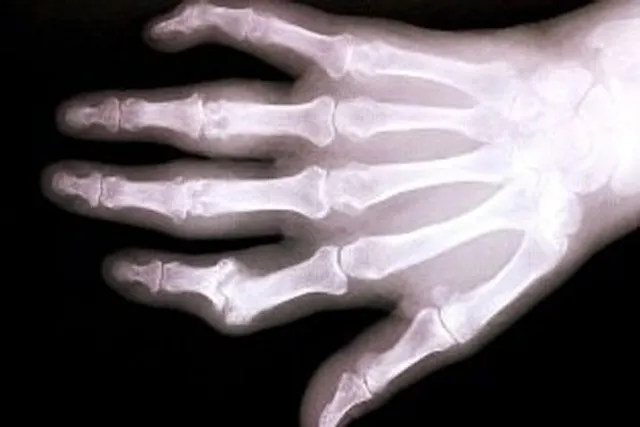

Osteoporosis is a medical condition in which the bones become brittle and fragile from loss of tissue, typically as a result of hormonal changes, or deficiency of calcium or vitamin D.